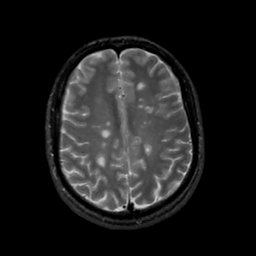

Tour 1: Next/Previous/Start: Now look at the temporal movie at this level, and you will see three lesions of approximately the same size, which appear and nearly disappear, along with the associated halo of edema. The 3 foci of inflammitory activity are clearly not in synchrony. Notice the left lower lesion: it is at the base of the marginal sulcus and occupies white matter under the right post-central gyrus. As the acute inflammation grows, notice how the architecture of the post-central sulcus is displaced posterolaterally. Near the end of the year, this lesion has almost disappeared, but another has appeared just behind it, in the slice below. In Tour #2, we will consider a lower, periventricular slice, in which a large range of lesion size is seen.

[Home][Help][Clinical][Tour 1][Tour 2] Slice 35